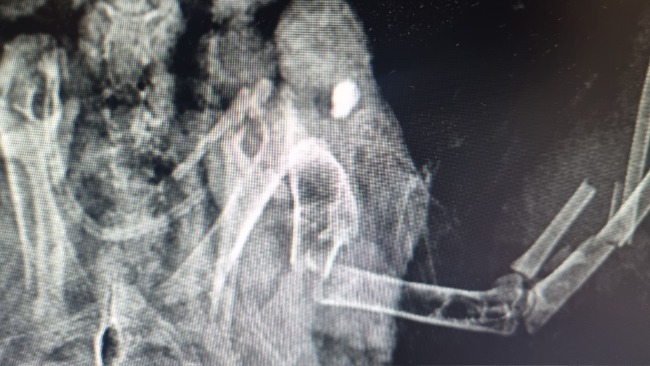

Właściciela posesji miała rację - ptak ma w sobie świeży śrut, który rozerwał mu jedno skrzydło, które jest całkowicie połamane. Dobrze się przyglądając, można zobaczyć ranę wlotową 😭😭😭

⚠️ Cel był celny. Tak jak okrucieństwo,, sadyzm, brak empatii, zwykłego zwyrodnialca, który z zabawy uczynić sobie okrutną rozrywkę. Oczywiście - z uwagi na dobre rokowania oraz sadystyczną krzywdę, której doznał, będziemy ratowali jego życie i sprawność. Patrzcie, jaki jest piękny i dobry dla ludzi.